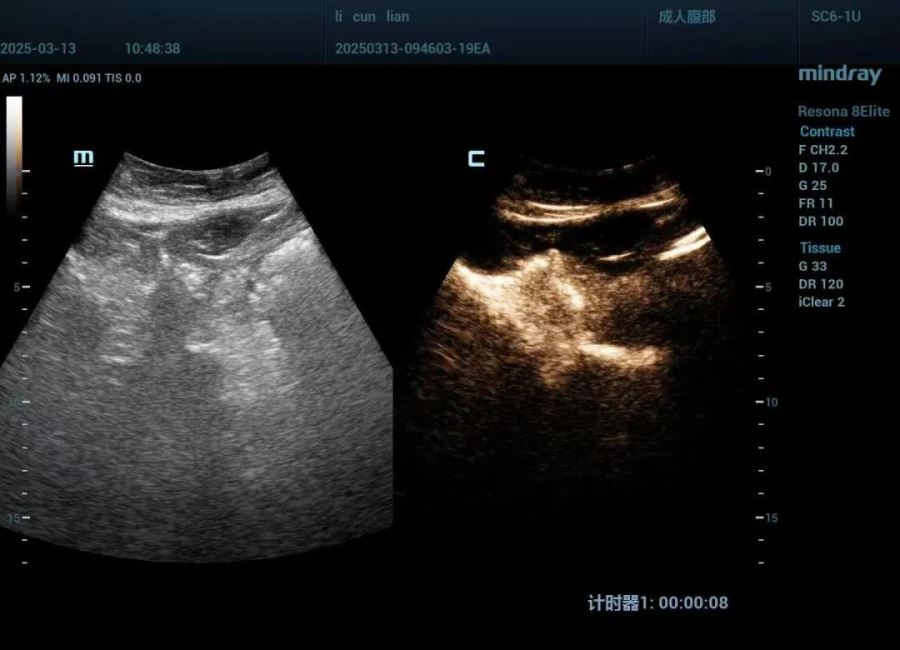

手术过程中,超声科团队在超声的精准引导下,将穿刺针准确置入肝左叶囊肿内,成功抽出约800ml黄色清亮液体,并注入稀释后的造影剂进行囊内造影。确认造影剂未进入肝内胆管及腹腔后,团队使用无水乙醇冲洗囊液至清亮,并注入了聚桂醇泡沫剂。整个手术过程顺利,李女士未出现任何不适反应,术后其右上腹症状完全消失。

手术前(肝囊肿直径约11cm)

手术后